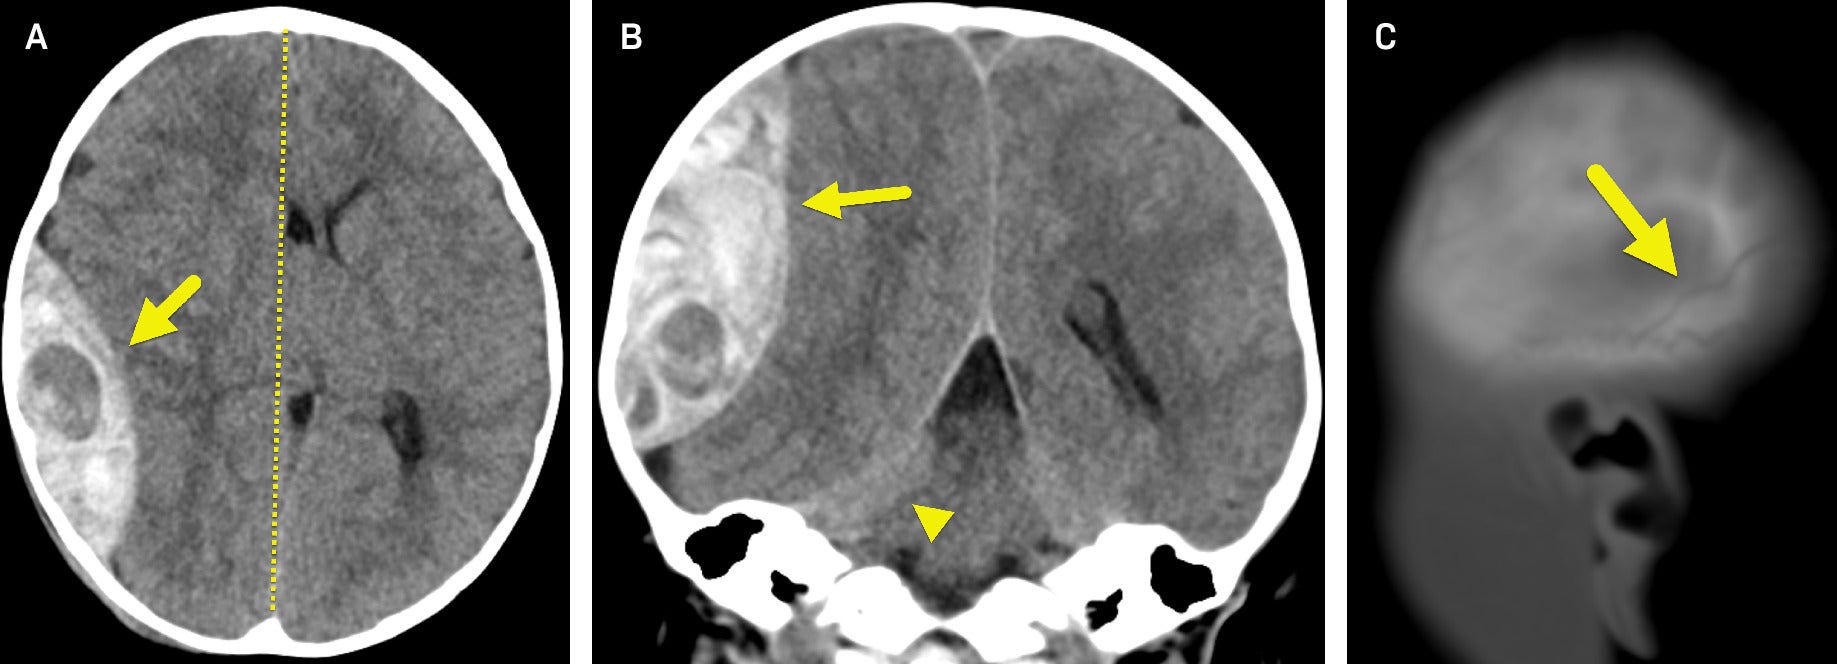

A non-contrast head CT ( Figure 1 ) revealed a large epidural hematoma (EDH) in the right parietal region. There was significant mass effect on the adjacent brain parenchyma with effacement of sulci and the right lateral ventricle, 11-mm right-to-left midline shift, and right uncal herniation. A nondisplaced calvarial fracture was present involving the posterior right parietal bone.

(A) Axial and (B) coronal non-contrast head CT show a large epidural hematoma (arrow) adjacent to the right parietal bone. The hypodense area within the large EH may represent active bleeding. There is a significant mass effect with a right-to-left midline shift (dashed line in A) and a right uncal herniation (arrowhead in B). (C) Sagittal CT image in bone window shows a nondisplaced skull fracture (arrow).